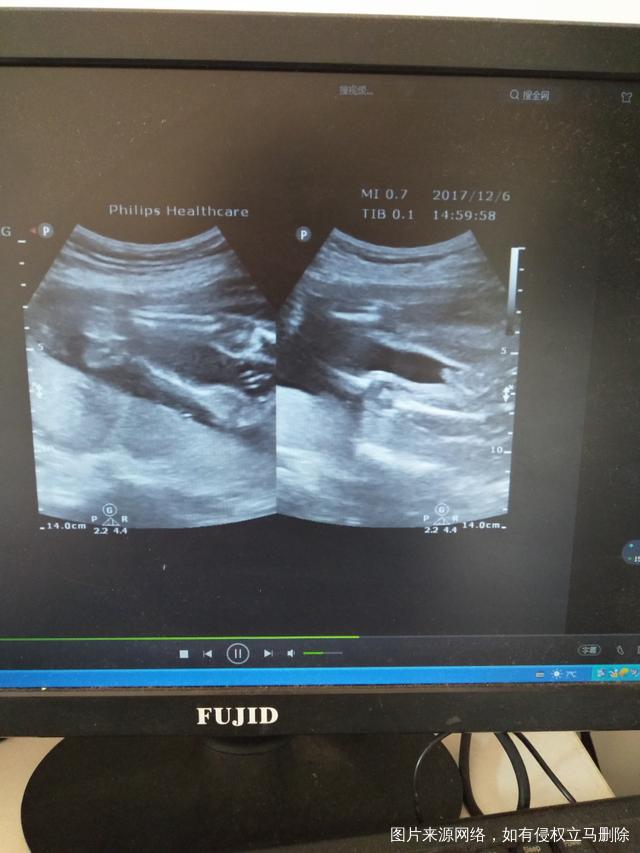

可以帮我看下是男孩还是女孩吗?